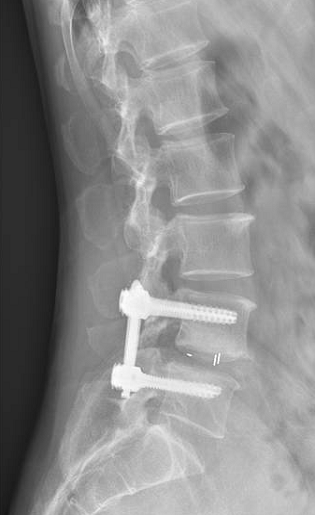

50歲的游先生因長期勞損,飽受腰痛與下肢放射痛折磨,保守治療無效,又因顧慮傳統(tǒng)手術創(chuàng)傷大、需植入螺釘而遲遲未決。我院脊柱團隊為其施行UBE下單側(cè)入路雙側(cè)減壓+椎間盤摘除+神經(jīng)根松解術,手術僅耗時50分鐘,術后24小時即可下床,3天出院,1個月后順利重返工作崗位。 內(nèi)鏡下減壓后影像 術后切口 病例二:高齡多病患者的“安全之選” 76歲的徐老先生患有嚴重腰椎管狹窄伴滑脫,合并高血壓、糖尿病,手術風險極高。經(jīng)多學科協(xié)作,團隊采用UBE技術為其完成減壓、復位、融合與內(nèi)固定,術中出血僅30毫升,無并發(fā)癥發(fā)生。術后第3天,老人已能下地行走,一周出院,家屬特贈錦旗致謝。 內(nèi)鏡下置入融合器 術后切口 術后DR片見滑脫已復位 病例三:復雜結(jié)核感染患者的“精準施治” 72歲的劉奶奶曾因椎體骨折接受骨水泥手術,后確診腰椎結(jié)核伴椎管內(nèi)膿腫,且體質(zhì)虛弱、伴有低氧血癥與貧血。團隊果斷采用UBE行椎管減壓+膿腫清除+骨水泥取出術,以微小切口解決重大隱患,術后患者疼痛顯著緩解,恢復良好。 術中取出椎管內(nèi)干酪樣膿腫 術中取出的骨水泥